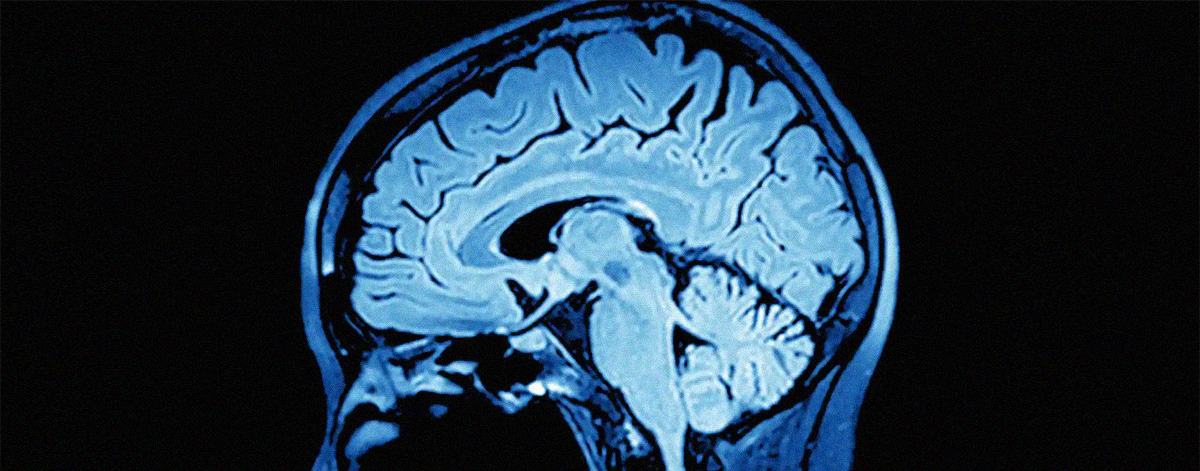

ეს ყველაფერი იმიტომ, რომ მკვლევართა აზრით, ჩვენი ტვინი ძალ-ღონეს არ იშურებს, რაც შეიძლება ნაკლებად ვამახვილებდეთ ყურადღებას გარდაუვალი სიკვდილის შესახებ ფიქრებზე.

კვლევის მიხედვით, ტვინი ეგზისტენციალური შიშისგან გვიცავს და სიკვდილს წარმოიდგენს, როგორც უბედურ შემთხვევას, რომელიც მხოლოდ სხვებს შეიძლება დაემართოთ.

“ტვინს არ სურს იმის დაშვება, რომ სიკვდილი ჩვენც გვემუქრება და როდესაც ამის შესახებ ინფორმაციას იღებს, მყისიერად რეაგირებს, განდევნის ფიქრებს ისე, თითქოს ეს ჩვენ არ გვეხებოდეს”, – ამბობს ნეირომეცნიერი იარ დორ-ზიდერმანი.

იმის დასადგენად, თუ როგორ უმკლავდება ტვინი სიკვდილის შესახებ ფიქრებს, დორ-ზიდერმანმა თანამშრომლებთან ერთად შეიმუშავა ტესტი, რომელიც გულისხმობდა ტვინში მოულოდნელი სიგნალების გამოწვევას.

მეცნიერებმა დაადგინეს, რომ თუ ცდისპირი ხედავდა საკუთარ სახეს სიკვდილთან ასოცირებულ სიტყვებთან ერთად, ტვინი თიშავდა პროგნოზირების მექანიზმს. ის უარს ამბობდა საკუთარი თავის სიკვდილთან დაკავშირებაზე და არც მოულოდნელ სიგნალებს აფიქსირებდა.